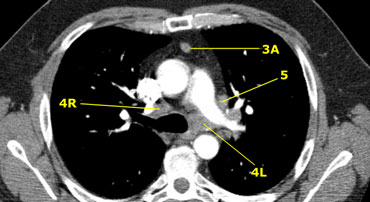

On the left a 3A node in the prevascular space.

Notice also lower paratracheal nodes on the right, i.e. 4R nodes.

On the left an image just above the level of the pulmonary trunk demonstrating lower paratracheal nodes on the left and on the right.

In addition there are also station 3 and 5 nodes.

On the left an image at the level of the lower trachea just above the carina.

To the left of the trachea 4L nodes.

Notice that these 4L nodes are between the pulmonary trunk and the aorta, but are not located in the AP-window, because they lie medially to the ligamentum arteriosum.

The node lateral to the pulmonary trunk is a station 5 node.